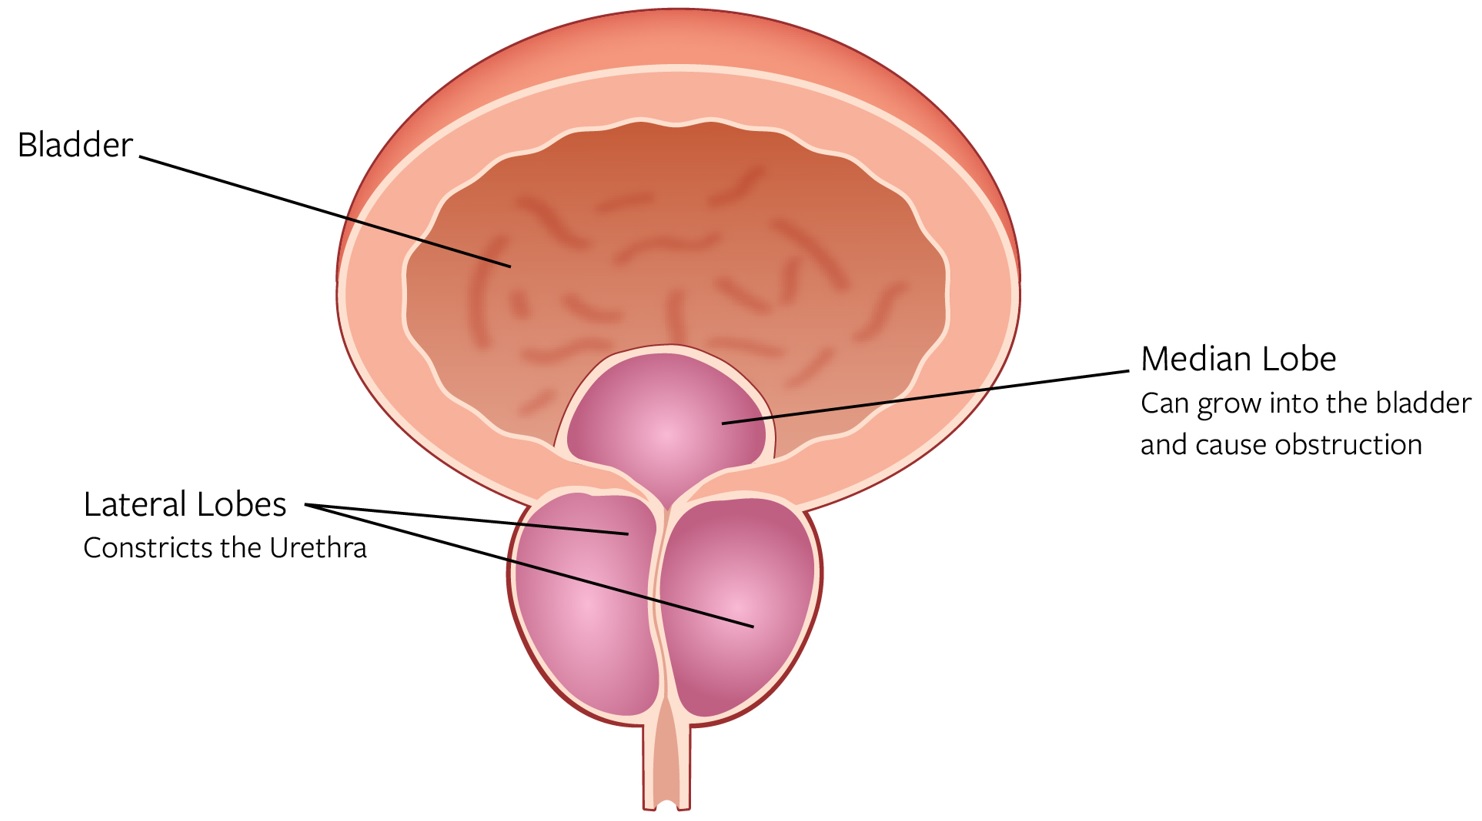

•Outcomes independent of prostate size and shape and surgeon experience. We designed Aquablation therapy to deliver outcomes that are effective, safe and durable for males suffering from LUTS due to BPH across all prostate sizes and shapes. Our WATER, WATER II and OPEN WATER studies enrolled men with prostate sizes between 20 ml and 150 ml; however, in the commercial setting, we have successfully treated men with prostate sizes over 300 ml. Additionally, in the WATER and WATER II studies, 50% and 83% of men, respectively, had an obstructive median lobe, and the average prostate size in each study was 54 ml and 107 ml, respectively. Compared to other resective procedures, we believe Aquablation therapy is relatively simple to learn, enabled by the intuitive user interface of the conformal planning unit, or CPU, and automated robotic resection, and delivers outcomes that are independent of surgeon experience.

BPH Disease Overview and Diagnosis

BPH refers to the non-malignant enlargement of the prostate gland. As the prostate enlarges, the gland presses against the urethra, which may obstruct or restrict the flow of urine from the bladder and result in uncomfortable LUTS, such as urgency, frequency, urinary retention, straining to urinate and a weak urinary stream. Without treatment, prolonged obstruction may eventually lead to acute urinary retention, urinary tract infections or renal insufficiency. An enlarged prostate can range between roughly 30 ml to above 300 ml. As prostates increase in size so does the complexity of shape where the obstructive tissue will grow back into the bladder (called an intravesical component).

Normal Prostate versus Enlarged Prostate